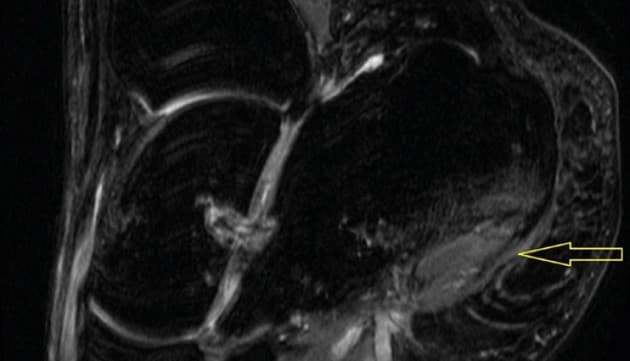

Patologisk senepåvirkning ved behandling med makrolider er en sjælden, men kendt bivirkning og rammer oftest akillessenen. Kasuistikken af Alzubadi et al beskriver udviklingen af bilateral fasciitis plantaris hos en 42-årig mand uden reumatologisk sygdom, som blev behandlet med tre dages kur med azithromycin på mistanke om infektiøs gastroenteritis. Forfatterne konkluderer, at det er vigtigt at overveje andre årsager til tendinopatier end overbelastning af vævet, reumatiske lidelser og tilstande som adipositas, diabetes mellitus, kronisk nyresvigt og forhøjet kolesterolniveau.

Bilateral fasciitis plantaris efter behandling med azithromycin